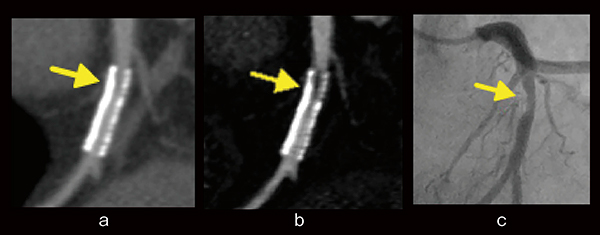

弊社の開発した心臓CTにおける画像再構成技術は,IQonをはじめとするフィリップスCTに搭載されており,独自のアルゴリズムにより画像再構成が可能である。フィリップスの心拍変動対応技術“Beat to Beat Variable Delay Algorithm”は,心拍変動が出現した場合に,基準心拍の任意の心位相に自動補正することで,RR間隔が異なる不整脈症例においても冠動脈の連続性が高くバンディングアーチファクトが少ない画像を提供することが可能となる。また,自動分割再構成技術“Adaptive MaxCycle”では,画像再構成中にセグメント分割数と分割比率を自動可変処理することで,モーションアーチファクトが少ない診断精度の高い画像を得ることできる(図6)。

図6 多様な心拍に対応する画像再構成技術

平均HR 96bpm(Af:心拍変動幅60〜125bpm)

(画像ご提供:みなみ野循環器病院様)